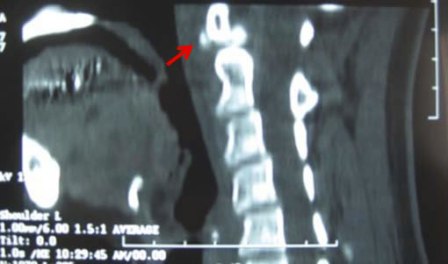

頚長筋 石灰化 (484 無料写真)

咽後膿瘍が疑われた急性石灰沈着性頸長筋腱炎の1例臨牀透析 34巻9号医書.jp。

感染症との鑑別が困難な石灰沈着性頸長筋腱炎 - 医療法人信岡会 菊池中央病院。

咽後膿瘍と鑑別を要した石灰沈着性頸長筋腱炎の3例臨床雑誌整形外科 63巻3号医書.jp。